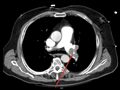

| Figure e34-50 Large bilateral pulmonary emboli (intravascular filling defects in contrast scan identified by red arrows). | |